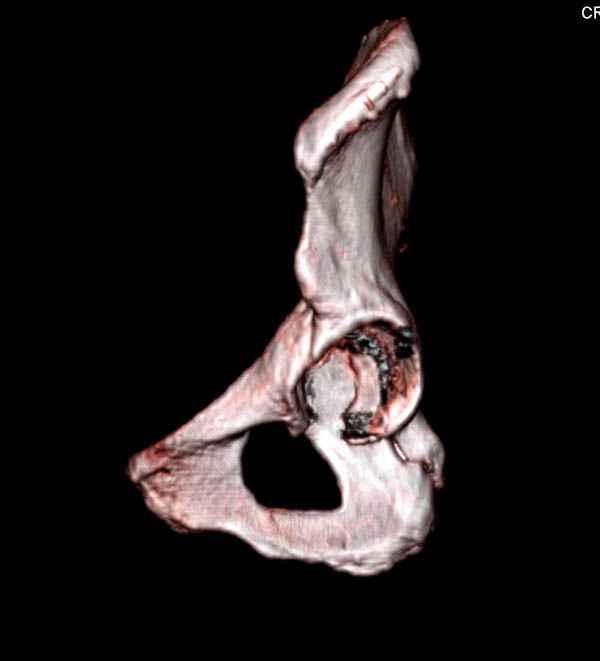

Уважаемые коллеги! С прошедшеми Вас праздниками. Теперь ближе к трудовым будням. Поступила 16 летняя девушка неделю назад. Механизм травмы падение с 5 этажа. Краткий диагноз:закрытый перелом левой ключицы, левого плеча, закрытый вертикально и ротационно нестабильный перелом костей таза:закрытый перелом левой подвздошной кости, переломы лонной кости справа, перелом обоих колонн вертлужной впадины слева;субкапитальный перелом шейки левой бедренной кости со смещением. По тактике лечения таза возникли следующие вопросы: 1. С чего начать - фиксации переломов вертлужной впадины или устранения деформаций таза? 2. Надо ли фиксировать шейку или фиксировать бедро в аппарате вместе с тазом, а после сращения таза планировать ТЭП ТБС? Если имеются еще какие подводные камни, будем рады выслушать.Спасибо.

На снимке ацетабулума редко встречающийся очень низкий перелом, наверное, трудно было репозицию через один доступ? Перелом как бы замкнулся в квадрилатеральной поврехности.